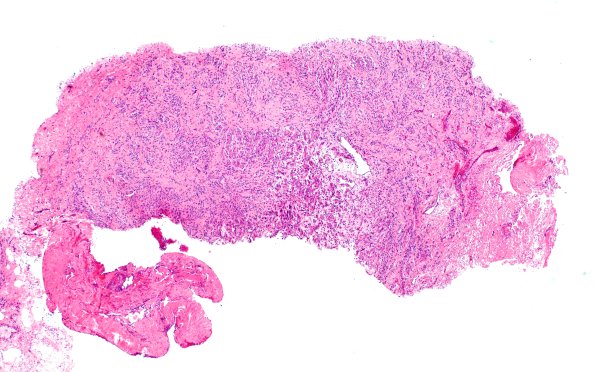

Washington University Experience | PERIPHERAL NEUROPATHY | 19 TRAUMATIC INJURIES | 23A1 Neuroma (Case 23) H&E 4X A

Case 23 History ---- The patient is a 29-year-old man with persistent pain and an upper trunk neuroma post-brachial plexus injury as part of a motorcycle accident. ---- 23A1-3 H&E-stained sections of the nerve biopsy material show an aggregate of innumerable 'mini fascicles' of nerve, consistent with a neuroma. These miniature fascicles are separated from each other by small bands of fibrous tissue, and in some areas appear more as single cells than true fascicles. (H&E)